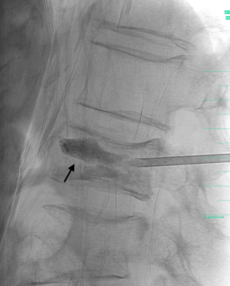

Bei der Vertebroplastie wird der Verlust an Knochenmasse durch Einspritzen von Knochenzement wieder ausgeglichen.Dazu wird in lokaler Betäubung mit einer Nadel vom Rücken her der Wirbelkörper punktiert. Dies geschieht unter ständiger Bildkontrolle durch den behandelnden Arzt.

Wenn die Nadel richtig platziert ist, wird, ebenfalls unter ständiger Bildkontrolle, der Knochenzement in den Knochen gespritzt.